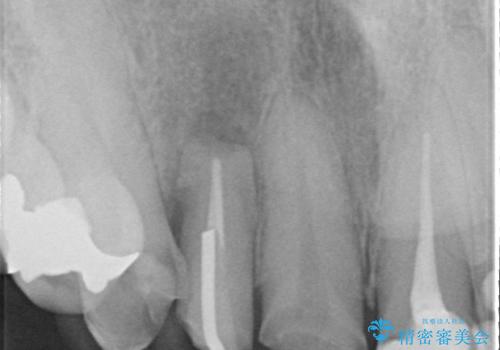

診査の結果右上2は歯根が破折しており、それが原因で骨及び歯肉の吸収が起きていました。

このまま右上2の抜歯を行うとさらに歯茎が下がる恐れがあったため、歯の挺出によって骨レベルを回復した上で抜歯し、歯槽堤保存術(抜歯窩に人工骨を填入する手術)を行いました。